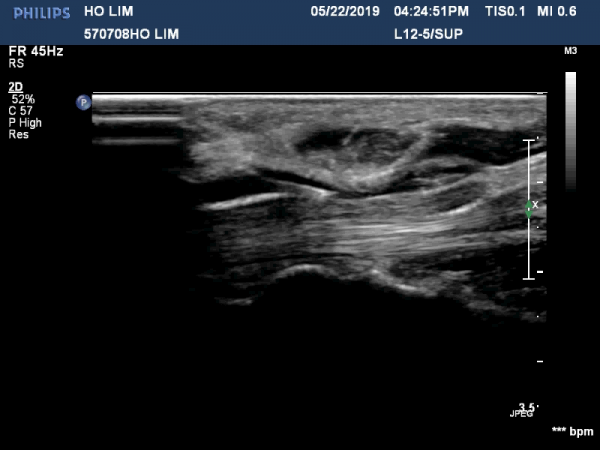

¼ö±Ù°ü ¸»´ÜºÎÀ§(trapezium, capitate level)¿¡¼ Á¤Á߽Űæ Ⱦ´Ü¸é°Ë»ç»ó Á¤Á߽ŰßÀÇ ÆíÆòȰ¡ °üÂûµÊ(»çÁø 3).

Á¤Á߽Űæ Á¾´Ü¸é°Ë»ç»ó ¼ö±Ù°ü ¸»´Ü(trapezium, capitate level) µÎ²¨¿öÁø Ⱦ¼ö±ÙÀδë(transverse carpal ligament)¿¡

ÀÇÇÑ Á¤Á߽ŰæÀÇ ±¹¼ÒÀû ¾Ð¹ÚÀÌ °üÂûµÊ(»çÁø 4, 5).

ÃÊÀ½ÆÄÀ¯µµÇÏ Á¤Áß½Å°æ ¼ö¾×¹Ú¸®¼ú(÷ºÎ »çÁø Âü°í) »çÁø¿¡¼ Á¤Á߽ŰæÀÇ Ç¥Ãþ¿¡ ÁÖ»ç¹Ù´ÃÀÌ À§Ä¡Çϰí

ÁÖ»çµÈ ¼ö¾×¿¡ ÀÇÇÑ È¾¼ø±Ù Àδ밡 Á¤Á߽Űæ°ú ºÐ¸®µÇ´Â ¸ð½ÀÀÌ º¸ÀÓ(»çÁø 6, 7, ÷ºÎÆÄÀÏ µ¿¿µ»ó). ½ÃÇàÇÏÁö ¾ÊÀ½.